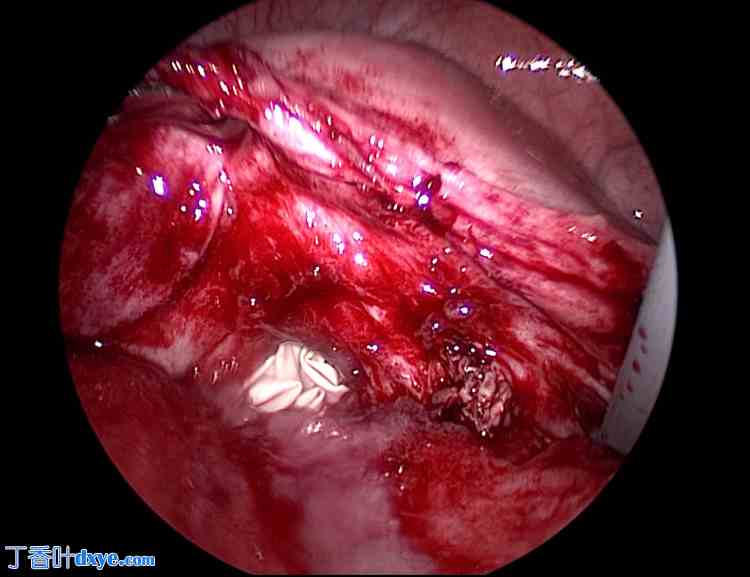

术中采用超声凝固装置,通过阴道内导管提起阴道前穹窿及后穹窿,切开阴道残端。阴道残端采用2-0多股合成可吸收缝线进行两层连续缝合(仅缝合阴道壁,不包括腹膜)(图1)。

图1. 阴道残端(首次手术)。